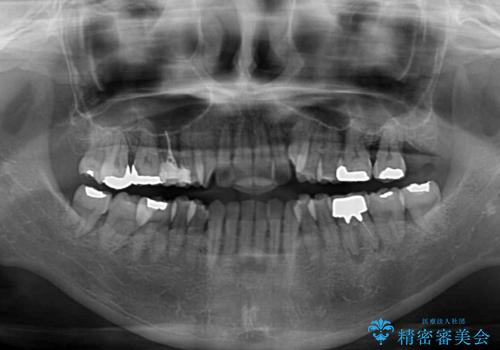

- 前歯のデコボコや八重歯を治したいとのことで来院された患者様です。

受け口傾向の骨格であり、前歯はクロスバイトまたは切端咬合となっており、下顎を中心に歯列全体の後方移動を行い、IPR(歯と歯の間を削る)によってデコボコが解消するように設計し、インビザラインにより治療を行うこととしました。